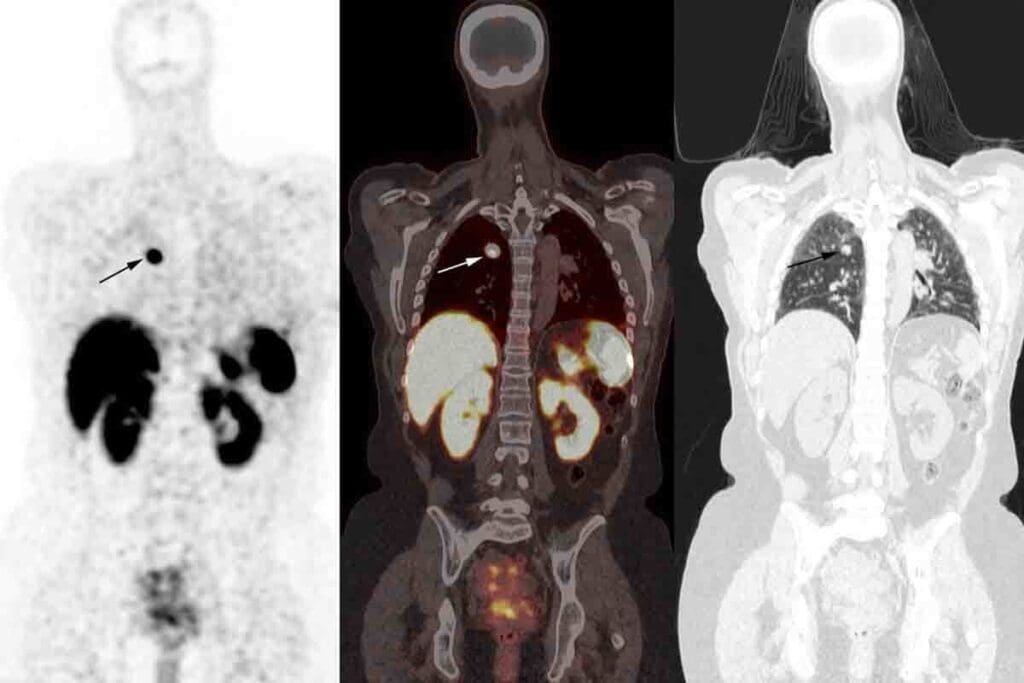

Imaging Process with the Gamma Camera

Once the radiotracer is in your system, you’ll move under a gamma camera. This camera picks up the radiation from the tracer in your kidneys. It takes pictures from different angles to show how your kidneys are doing.

The camera might take static images or moving pictures over time. This helps the team see how your kidneys are working and processing the tracer.